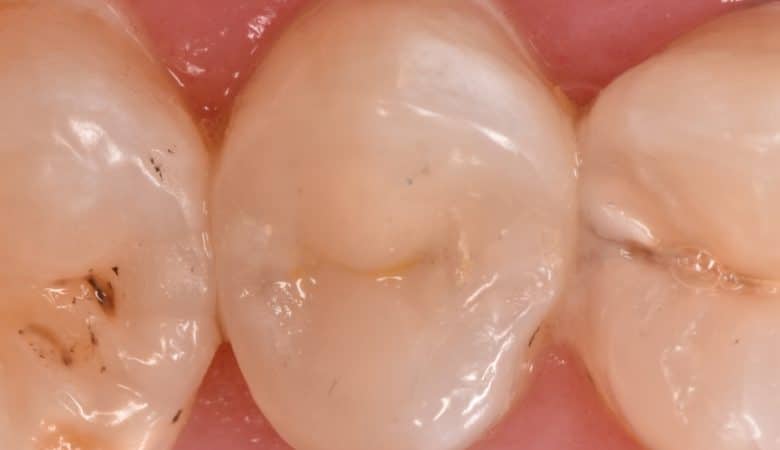

Lower 1st molar with old bad amalgam filling restored by direct composite restoration that reinforced by Ever X posterior for dentin replacement and moer strength to the filling When the patient can’t tolerate the cost of indirect lithium disilicate we…